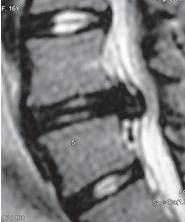

МРТ № 97

Иллюстрация к книге — Остеохондроз для профессионального пациента [i_116.jpg]

На МРТ № 97 у шестнадцатилетней пациентки наблюдается секвестрированная грыжа межпозвонкового диска в сегменте LIV-LV.